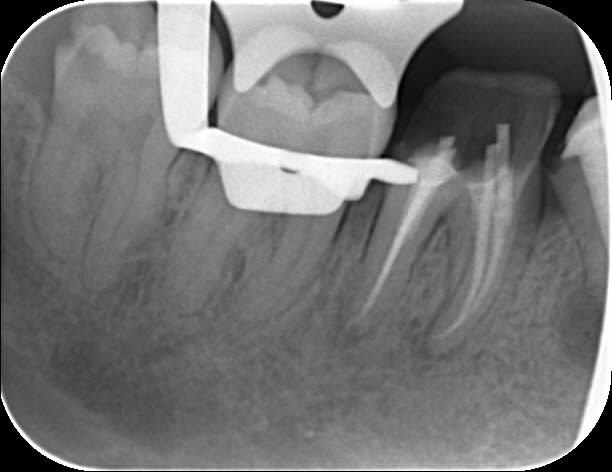

2 retraitements endo sur 45 46.

2 m85na9 - Eugenol

3 j2ewih - Eugenol

4 mbyxz8 - Eugenol

1 ojgvk3 - Eugenol